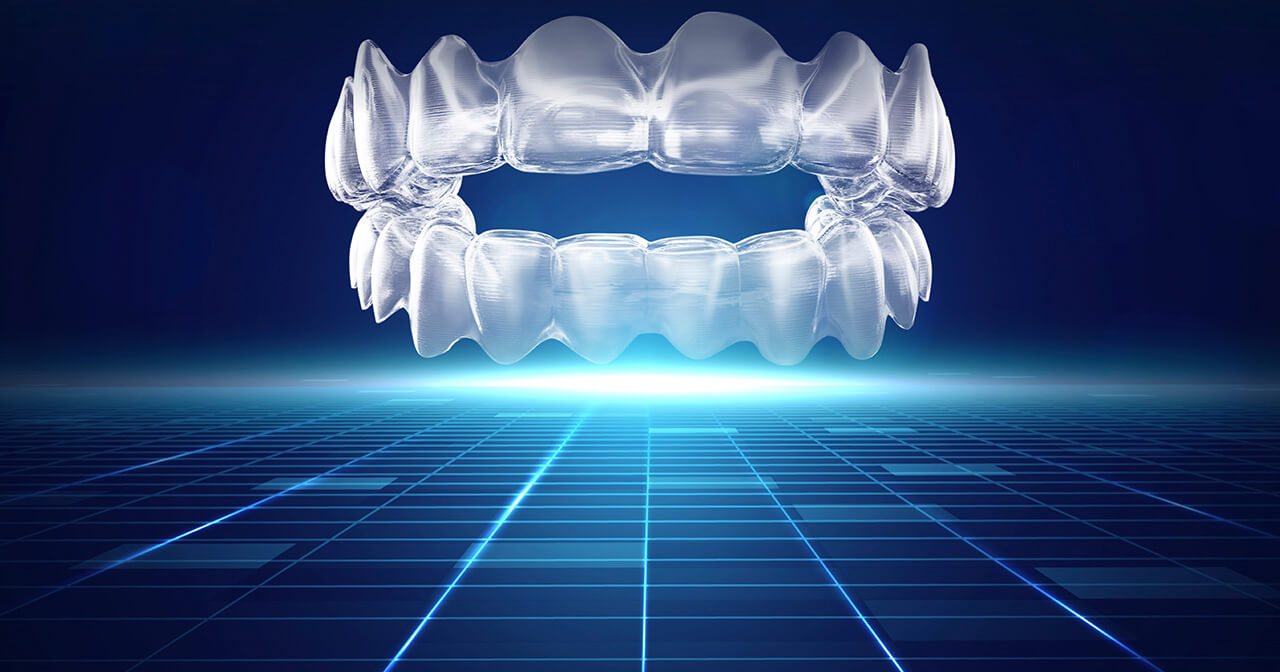

Amazing 6-month Smile Transformation

Dr Katyal’s Publications, Uncategorised

Here is a 6 month smile finished with clear aligners in an adult female. One of the concerns with expansion in adult cases is gingival recession and lifetime stability. To understand the soft tissue limits of tooth movement there is nothing better than good old Dr Proffit’s Envelope of Discrepancy. It’s simply a guideline but a powerful one on limits of tooth movement in various directions.

A big tip here is to add extra buccal root torque to your digital treatment simulations per mm of transverse expansion for upper molars and premolars. Finishing of a case to a high aesthetic degree is very important. To achieve the correct angulations and torque for anterior teeth is always a challenge for even a highly skilled orthodontic clinician. Clear aligners managed well can also give an efficient and predictable finish.

Accuracy studies for clear aligners are often flawed. They are often comparing a single Clincheck or measuring against a prediction rather than a real-time simulation.

Newer unpublished studies from various universities around the world presented at conferences are starting to show a promise of increased accuracy with clear aligners, especially when using 3D virtual tracking on a routine basis for orthodontic patients.